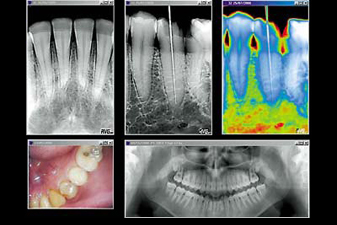

Hawa Dental uses digital X-Rays for your safety, as well as for more accurate diagnosis. Digital X-Rays emit far less radiation and allow the doctor and patient to see small details in your teeth and gums.